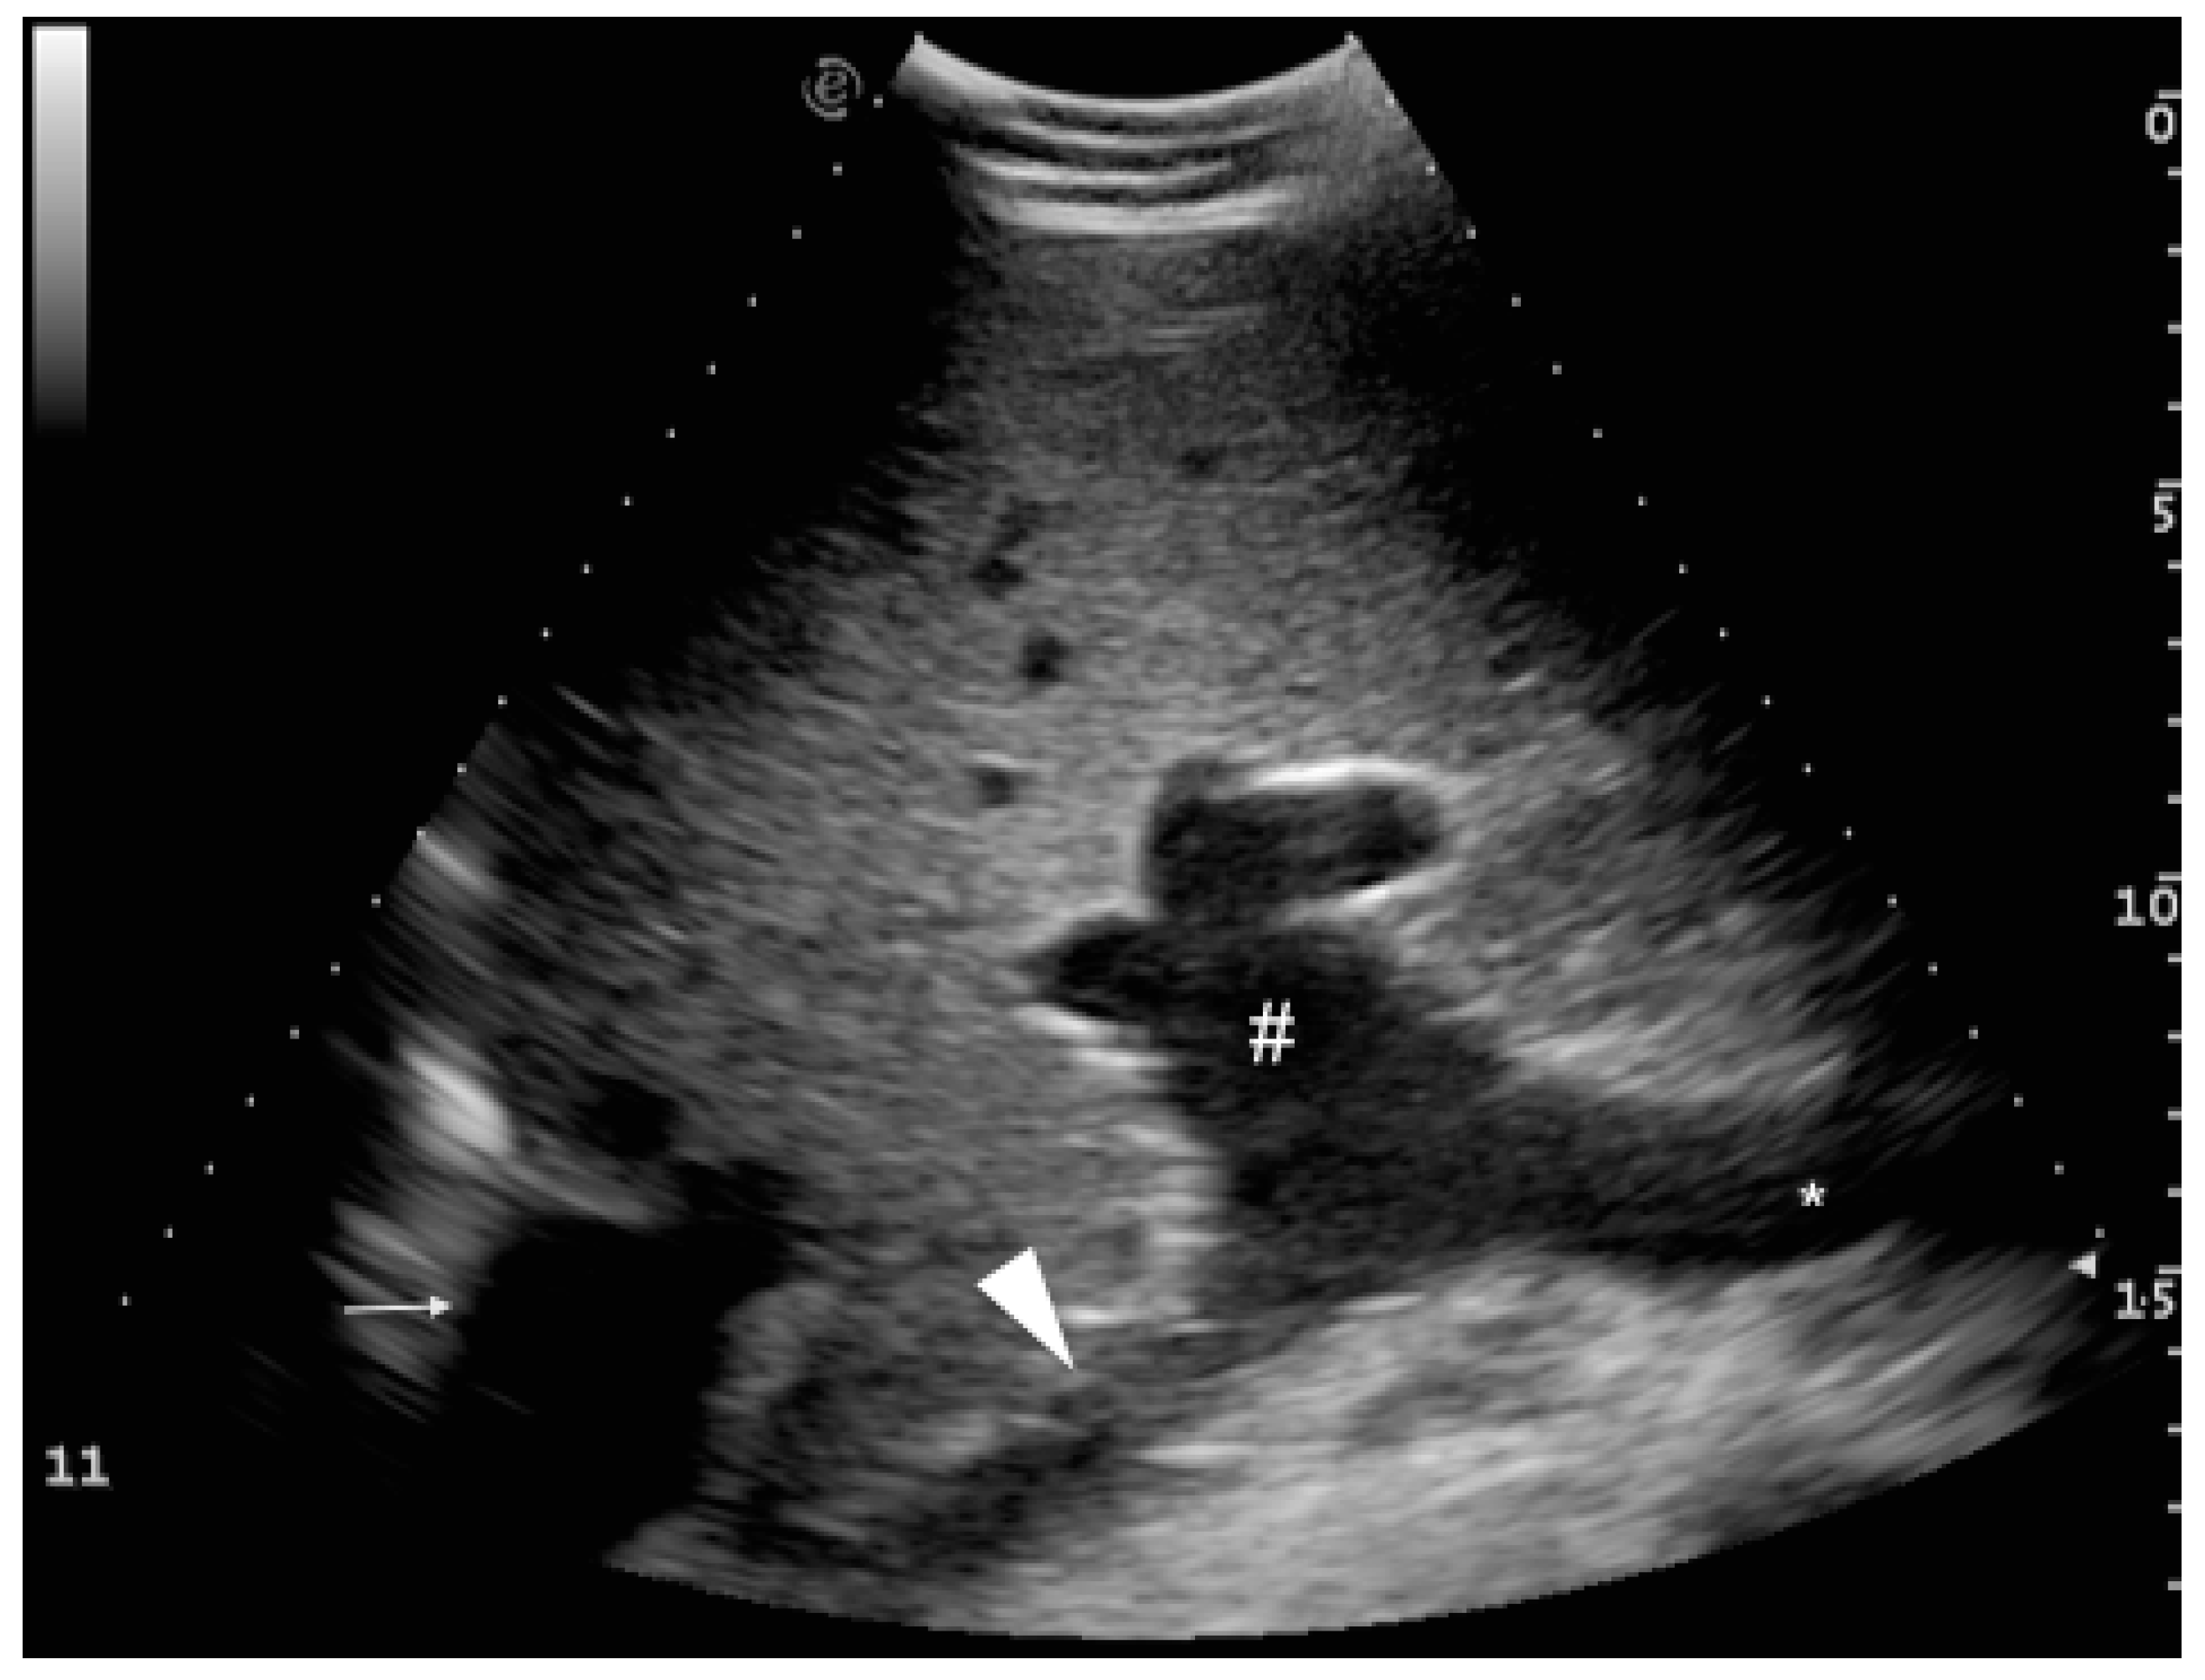

3.2. Portal System